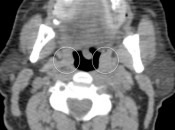

- Bladder in Inguinal Canal